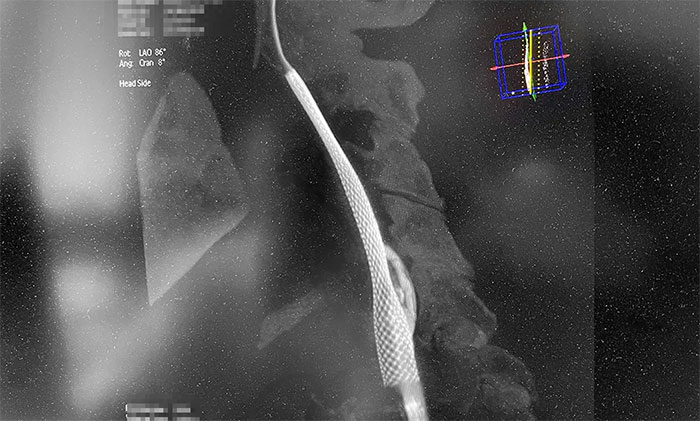

术中,超滑导丝、多功能导管经过反复尝试顺利通过左颈内动脉起始段,到达左颈内动脉远端显影段,路图见远端血管通畅,左大脑中动脉显影;随后,微导丝经多功能导管置于左颈内动脉海绵窦段,经微导丝送入保护伞至左颈内动脉岩骨垂直段并释放,再沿保护伞微导丝送入4x30mm球囊于左颈内动脉起始段,给予球囊扩张,撤除球囊后造影见左颈内动脉起始段再通,左颈内动脉、左大脑中动脉显影;最后,送入9x50mm支架,释放于左颈内动脉颈段至左颈总动脉末段,造影见左颈内动脉起始段显影明显改善,左颈内动脉、左大脑中动脉、左大脑前动脉显影可,行3D造影见左颈内动脉颈段显影改善。行支架CT见支架成形可,行XperCT未见颅内出血。